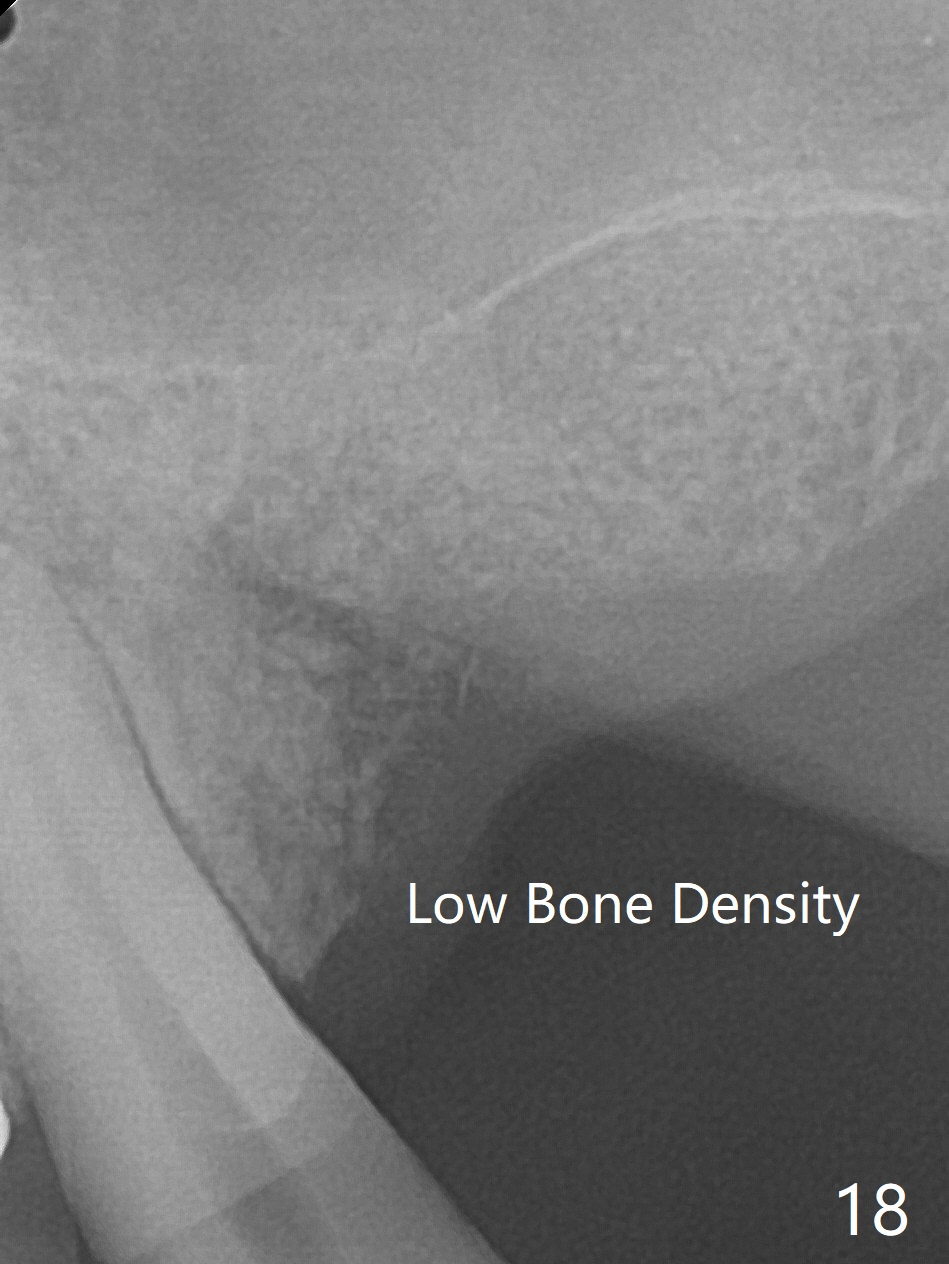

The bone density of the site is low 4 months post bone graft (Fig.17,18). Use the existing guide, but incision will be made. The osteotomy will be underprep. Take 5x5 cm CT for bone width and height after use of 2.2x7.3 drill with 1 or 2 O-rings. Prepare sinus lift, including water pump and bone graft, especially distal. Place healing screw and suture. Prepare PRFx2.